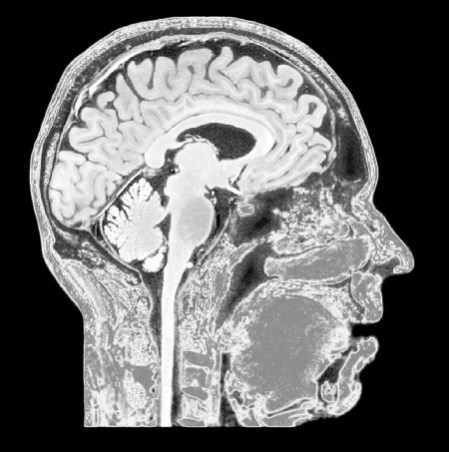

Ствол мозга и мозжечок образуют задний мозг и поддерживают в нас жизнь. Мозжечок В основании мозга расположена структура, похожая на скорлупу грецкого ореха. Ее называют мозжечком. Из-за схожести названий (cerebellum) его часто путают с конечным мозгом (cerebrum). Мозжечок, что в переводе с латыни означает «маленький мозг», является самой крупной структурой заднего мозга. Он управляет произвольными движениями мышц. Также мозжечок помогает поддерживать осанку и равновесие – за счет обработки нервных импульсов от сенсорных систем (например, внутреннего уха) и согласования с ними положения наших мышц. В отличие от остальных мозговых структур, левая половина мозжечка управляет левой половиной нашего тела. Это возможно благодаря парной работе с правым полушарием головного мозга. Злоупотребление алкоголем или деформация от опухоли или инсульта могут повредить мозжечок. Кроме того, на работу мозжечка влияют такие заболевания, как церебральный паралич и рассеянный склероз. Сопутствующие симптомы повреждения включают неустойчивую походку, рассогласованность движений мышц, невнятную речь и проблемы с выполнением точных движений. Средний мозг Средний мозг – это небольшая область в верхней части ствола мозга. Он играет важную роль в соединении заднего и переднего мозга. Средний мозг помогает обрабатывать входящие визуальные и звуковые сигналы, координирует движения и управляет болью. К важным структурам среднего мозга относятся крыша, покрышка и ножки мозга. В них содержится скопление пигментированных нейронов (их называют ядрами ЦНС), которые вырабатывают нейромедиатор дофамин. Эта темная область, или черное вещество, активно участвует в «системе поощрения» и движении. ![]() Болезнь Паркинсона связана с сокращением количества дофаминергических нейронов в черном веществе. Гибель дофаминергических нейронов приводит к различным заболеваниям и симптомам, например паркинсонизму и болезни Паркинсона. Считается, что повышенное выделение дофамина связано с развитием шизофрении. Было замечено, что пациенты лучше реагируют на лекарства, блокирующие дофаминовые рецепторы. В то же время люди, употребляющие амфетамины, которые также повышают уровень дофамина, проявляют те же симптомы, что и больные шизофренией. Однако есть и другие теории, оспаривающие это. Передний мозг Передний мозг – это все, что образовано конечным мозгом, за исключением среднего мозга. Иначе говоря, к переднему мозгу относятся кора головного мозга и подкорковые структуры: таламус, гипоталамус, базальные ганглии и лимбическая система. ![]() На рентгеновском снимке изображен сагиттальный участок мозга с четко видимыми структурами. У этого пациента кора головного мозга выглядит истонченной и усохшей, что является классическим признаком деменции. Кора головного мозга обрабатывает информацию, которая поступает от пяти органов чувств. Однако это не просто пассивный приемник; кора способна посылать команды в другие части нервной системы. Сенсорная и моторная (двигательная) зоны коры контролируют определенные участки тела, а четыре доли разделяют кору на функциональные части. Сенсорные области интерпретируют информацию, которую получают от органов чувств, а моторные зоны «говорят» скелетным мышцам, когда и как двигаться. Промежуточным звеном между сенсорной и моторной зонами являются ассоциативные области. Они анализируют полученную информацию и корректируют ее, прежде чем отправить дальше, в моторные области. Функции долей мозга Никто не знает автора этих строк, но часто говорят: «Если бы человеческий мозг был так прост, что мы могли бы его понять, то мы были бы так просты, что не смогли бы его понять». За эти годы мы достигли значительного прогресса в понимании организации и функций мозга и его долей. Но наука не стоит на месте, поэтому нам еще многое предстоит узнать. Пока что ясно лишь одно: мы живем, пока жив мозг; без него нас бы не было. ![]() ![]() ![]() ![]() Этот вид сбоку показывает основные функциональные зоны коры головного мозга. Основные функции каждой зоны приведены в таблице выше. Ты на меня смотришь? На изображении справа показано, как мозг «видит» вашу внешность. Этот образ не станет лучше, какой бы объектив не выбрал мозг: сенсорный или моторный. У вас так и останутся огромные руки, большие рот, язык и губы и маленькие туловище, ноги и голова. ![]() Эта диаграмма кортикального гомункула показывает, какими частями тела управляют определенные области мозга. ![]() «Гомункулус» на латыни означает «маленький человек». Человека-гомункулуса придумали американские нейрохирурги Уайлдер Пенфилд и Эдвин Болдри. Их работы, опубликованные в 1937 году, были посвящены пациентам с эпилепсией. Полученные данные позволили ученым составить карту различных областей мозга. Проекция-гомункулус показывает, как выглядел бы человек, если бы пропорции тела зависели от объема корковой области, выделенной мозгом. Такое искаженное изображение получается, потому что мозг разделяет соматосенсорную и моторную кору на области по степени иннервации органов, а не объему кожи или анатомической площади. Области тела с большим количеством чувствительных нейронов занимают крупные области коры, и, следовательно, такие области более чувствительны. Кровоснабжение мозга Наш мозг питают парная внутренняя сонная артерия и позвоночные артерии. Внутренние сонные артерии снабжают кровью переднюю часть мозга, а позвоночные артерии – заднюю. Позвоночная (теперь ее называют базилярной) и внутренняя сонные артерии после своего ветвления сходятся в нижней части головного мозга, образуя Виллизиев круг – кольцо из кровеносных сосудов, соединенных анастомозами. Виллизиев круг обеспечивает мозг кровью даже при сужении или закупорке одного из сосудов. В этом участке развивается большая часть аневризм. Если одна из таких аневризм лопнет, последует кровоизлияние в мозг. |